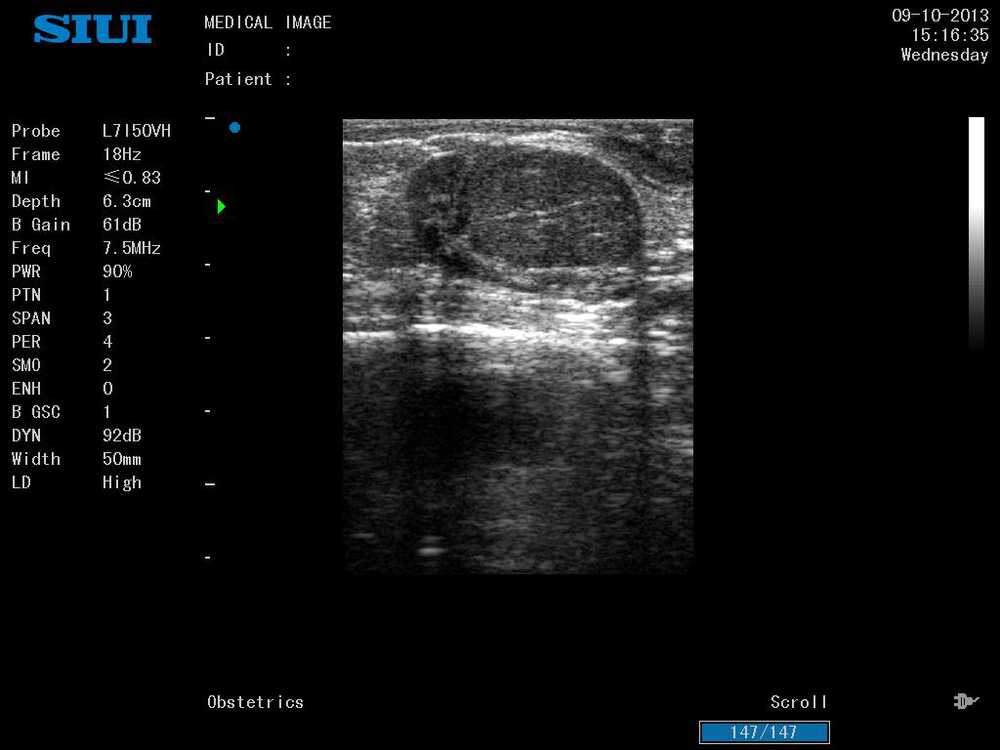

Após 30 dias pós-parto (D+30), durante exame de rotina realizado pelo médico-veterinário responsável, foi notado acúmulo de líquido no útero, palpação retal, porém, sem alteração dos parâmetros fisiológicos e hemograma dentro dos padrões esperados. No exame ultrassográfico foi confirmada a presença de substância com característica hiperecóica no lúmen uterino (fig. 1) e corpo lúteo (fig. 2).

Figura 2.